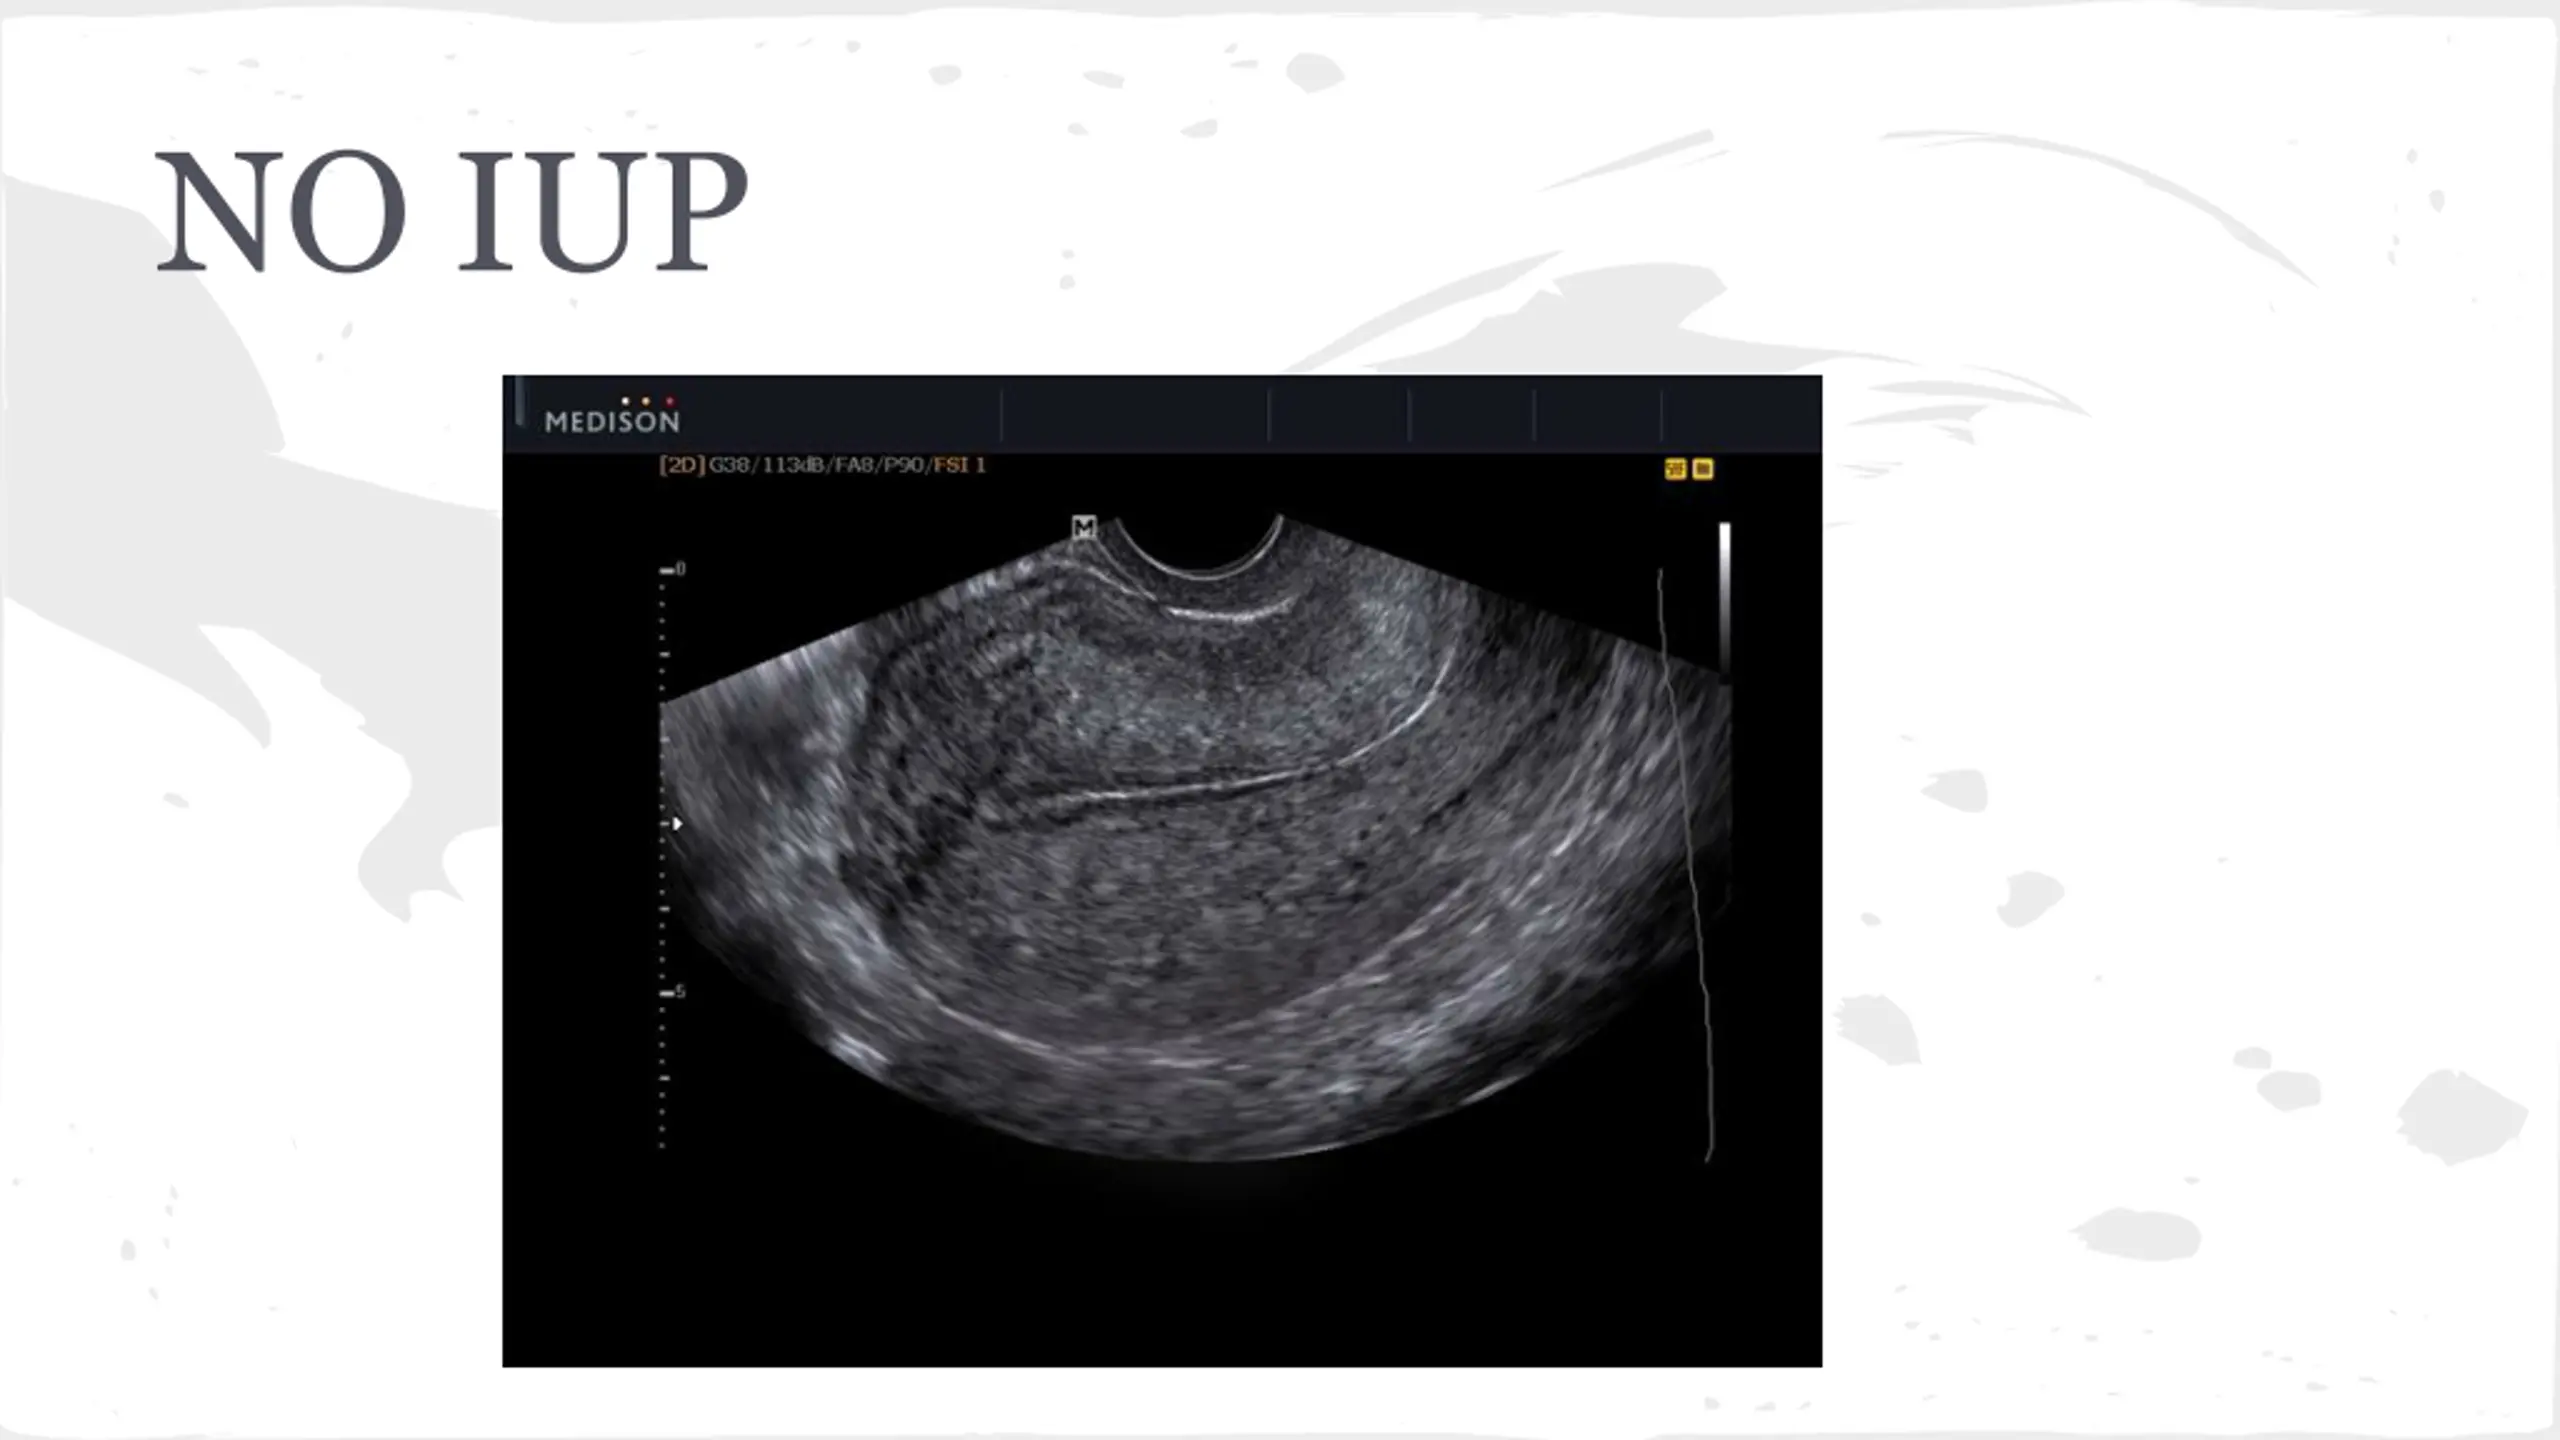

Ectopic Pregnancy-Likelihood Ratios CMT-4.9 Adnexal mass-2.4 Adnexal tenderness 1.9 Ultrasound-111 No IUP on US in pregant patient is ectopic until proven otherwise

Ectopic Pregnancy Symptoms Abdominal Pain Syncope Vaginal Bleeding Vomiting Exam Lower abdominal tenderness Adnexal TTP CMT Peritoneal Abdomen

Ectopic Pregnancy Labs Quant B-HCG, CBC, Coags, Type and Screen -very low B-HCG cannot rule out ectopic Management -STAT GYN consult -NPO -Medical vs Surgical Management